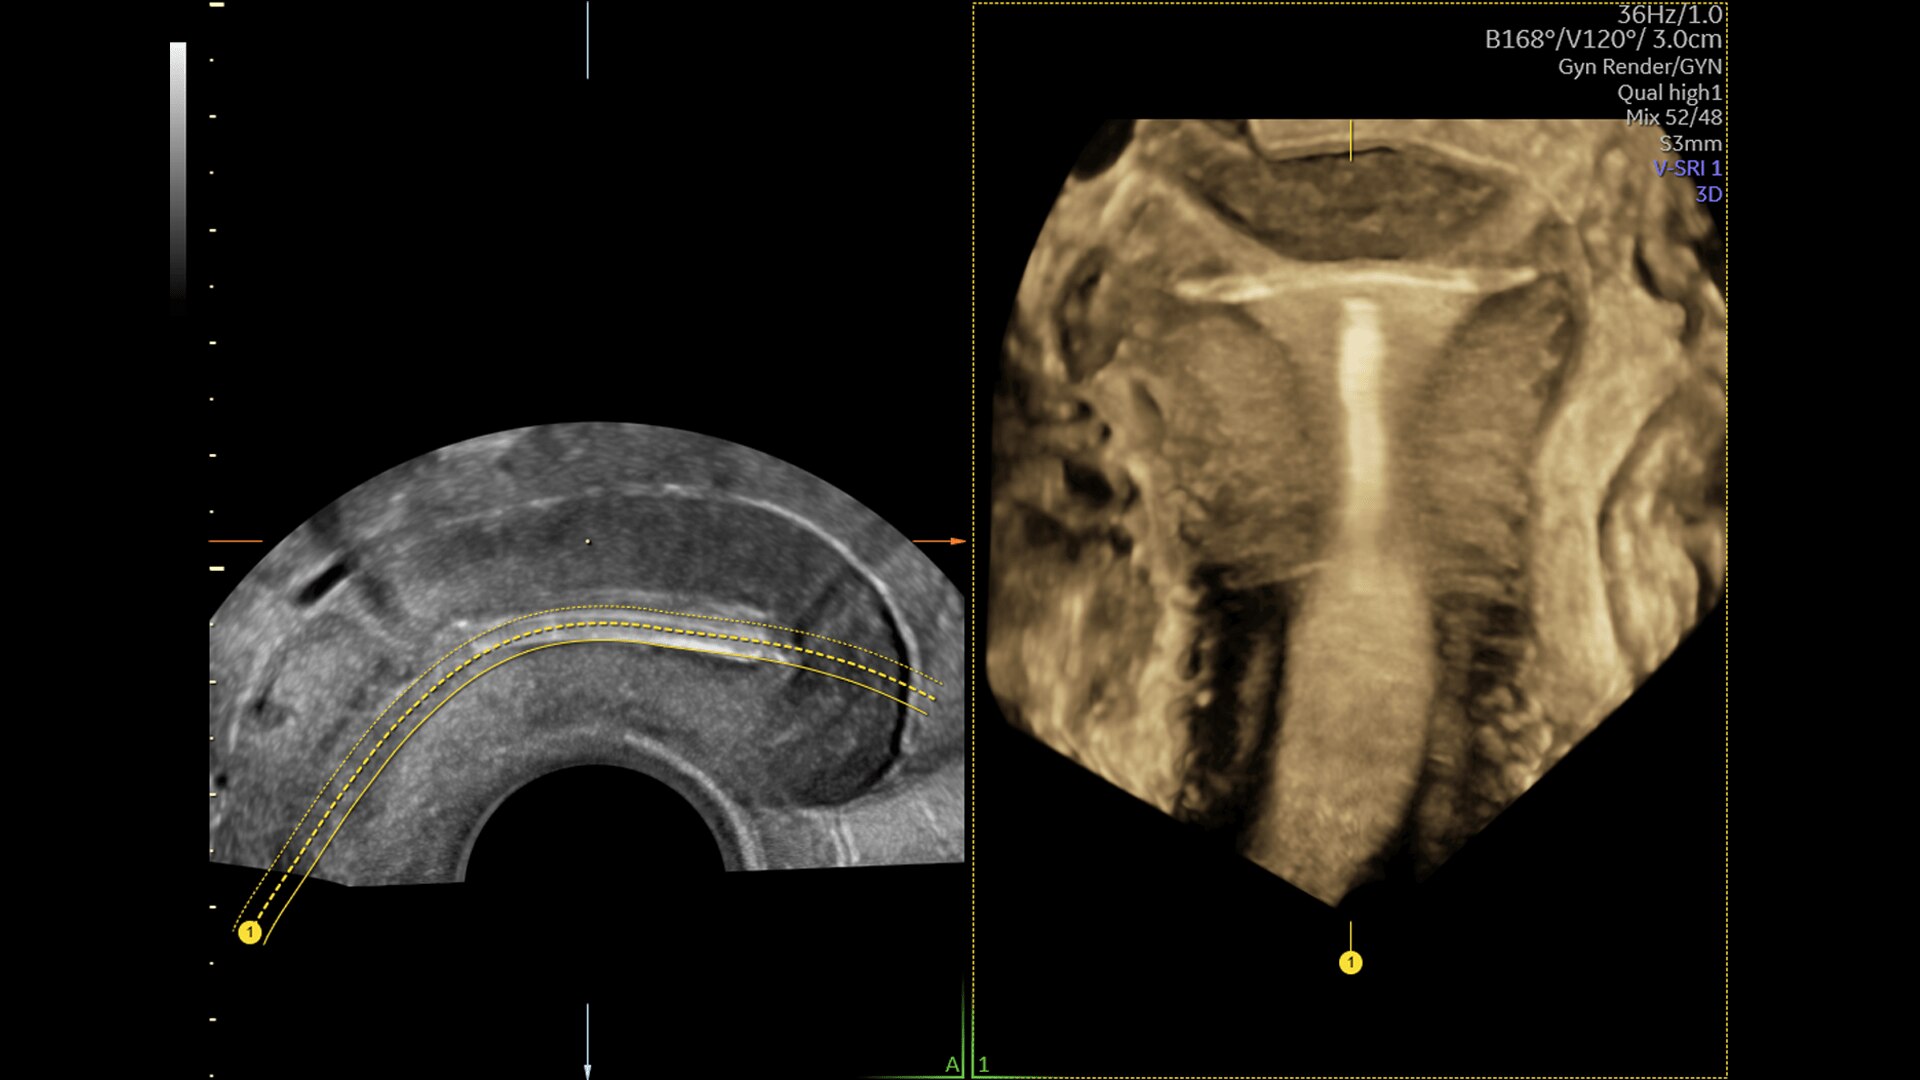

Voluson Expert 22 Imaging Capabilities

Experience next-level imaging capabilities that will help you see critical details required for confident diagnosis.

SPECTACULAR IMAGING

Find the Needle in the Haystack

How do you make our best ultrasound even better? Build a more powerful engine with the most progressive and adaptive capabilities yet. Our Lyric Architecture allows for more data — leading to higher spatial and contrast resolution and color sensitivity. It works in harmony with our specialized probe technology to extract more information at record speeds for faster, sharper, and clearer images.

Enhanced Volume Imaging

Deliver next generation 3D/4D & Color images with HDlive Studio+